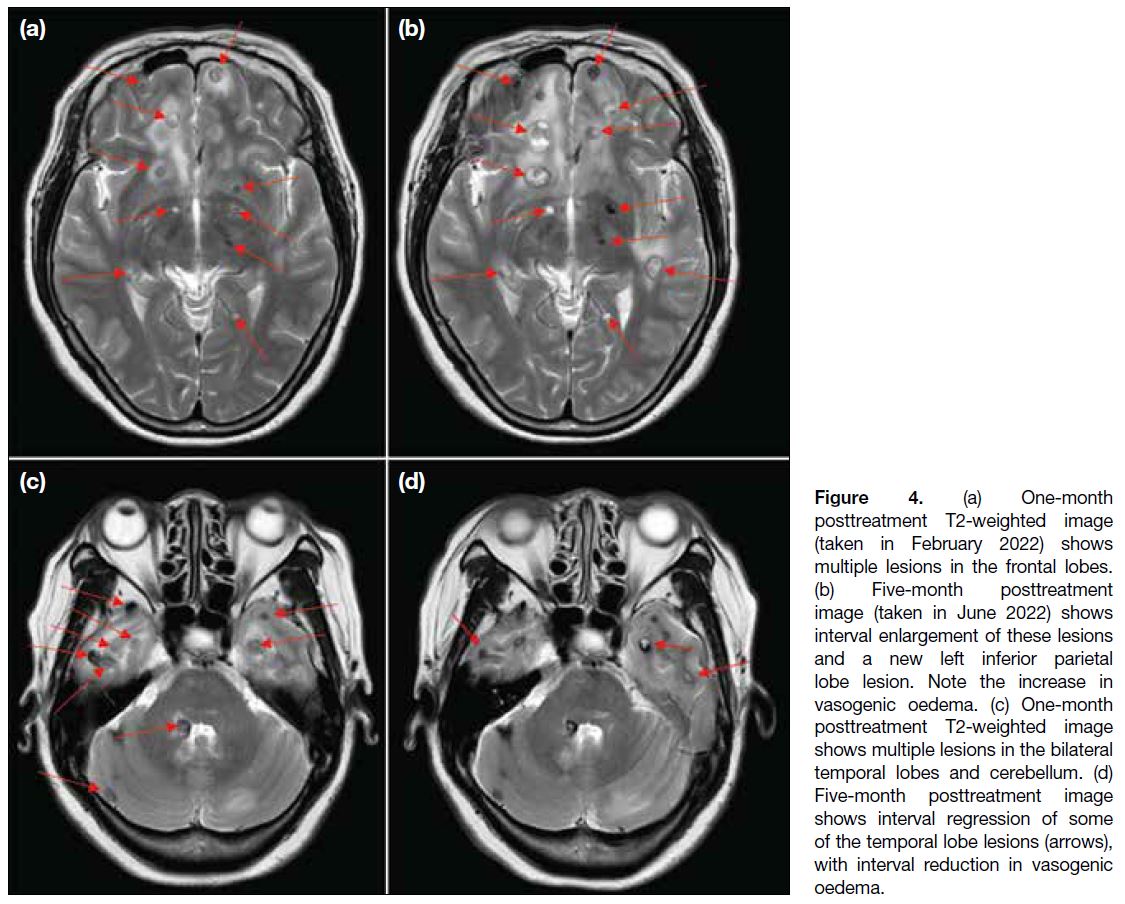

A scan at 5 months posttreatment revealed continued progression of some lesions in the bilateral frontal and left inferior parietal lobes (Figure 4a and b), while some lesions in the bilateral temporal lobes had regressed (Figure 4c and d). The overall picture favoured a mixed treatment response.

Figure 4. (a) One-month

posttreatment T2-weighted image

(taken in February 2022) shows

multiple lesions in the frontal lobes.

(b) Five-month posttreatment

image (taken in June 2022) shows

interval enlargement of these lesions

and a new left inferior parietal

lobe lesion. Note the increase in

vasogenic oedema. (c) One-month

shows multiple lesions in the bilateral

temporal lobes and cerebellum. (d)

Five-month posttreatment image

shows interval regression of some

of the temporal lobe lesions (arrows),

with interval reduction in vasogenic

oedema.